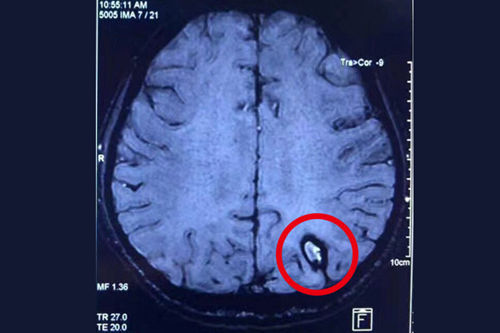

患者术前的磁共振影像: 红圈处为颅内海绵状血管瘤病灶